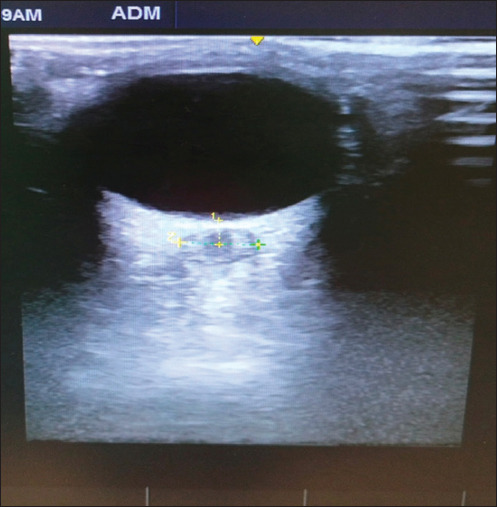

Background and aims: Laparoscopic surgery involves creation of carbondioxide (CO2) pneumoperitoneum leading to a rise in intracranial pressure (ICP), which can cause expansion of optic nerve sheath diameter(ONSD).We aimed to study the magnitude of changes in ONSD occurring during pediatric laparoscopic surgery and correlate them with changes in end-tidal CO2 (EtCO2), intrabdominal pressure (IAP), and a change in patient position (P).

Material and methods: Thirty-five pediatric patients between 1 and 12 years undergoing laparoscopic surgeries under general anesthesia were included.The ONSD, EtCO2, IAP, and position (P) in degrees from supine were recorded 15 min post-anesthesia induction(T1) and 30 min following the establishment of pneumoperitoneum (T2).The difference between the two groups was analyzed using a paired or unpaired t-test for quantitative variables and using Chi-square or Fisher's exact test for qualitative data.Correlation between two quantitative variables was performed using Pearson's correlation coefficient.

Results: Mean ONSD showed a significant change (P < 0.001) 30 min (T2) following pneumoperitoneum increasing by an average of 0.04cm as compared to 15 min (T1) post-anesthesia induction (0.57 ± 0.06 vs. 0.61 ± 0.06). There was a moderate to strong positive correlation between change in ONSD and change in EtCO2(correlation coefficient = 0.629, P = 0.001) 30 min post pneumoperitoneum. There was a weak correlation between change in ONSD and change in position (correlation coefficient = 0.276) and a very weak correlation between change in ONSD and change in IAP (correlation coefficient = 0.19).

Conclusions: Laparoscopic surgeries in children can cause significant increases in ICP as measured by the ONSD; changes in EtCO2 are the predominant factor responsible. Increasing minute ventilation to maintain normal EtCO2 may help mitigate changes in ICP in children undergoing laparoscopic surgery.